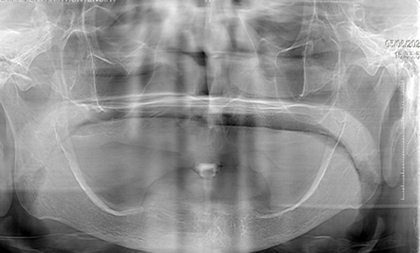

Fotografía del maxilar inferior (Figura 1).

Figura 1. Maxilar Inferior.

Elaboración: Los autores.

La paciente lleva usando una prótesis 10 años, debido a la irregularidad de rebordes que presenta la mandíbula, se considera desde el punto protésico un caso deficiente.

EXAMEN RADIOGRÁFICO

Paciente presenta elevaciones irregulares en el maxilar inferior (Figura 2).